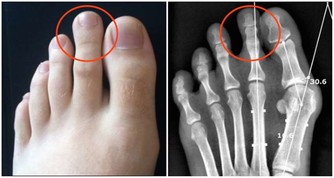

但這一“憋”,事就大了,不僅容易引起尿路感染,還可能引起腎盂腎炎,損害腎臟,導致膀胱癌。若是早上,人的各項生理功能維持著低速運轉,長時間憋尿易使心腦血管疾病患者發生意外。